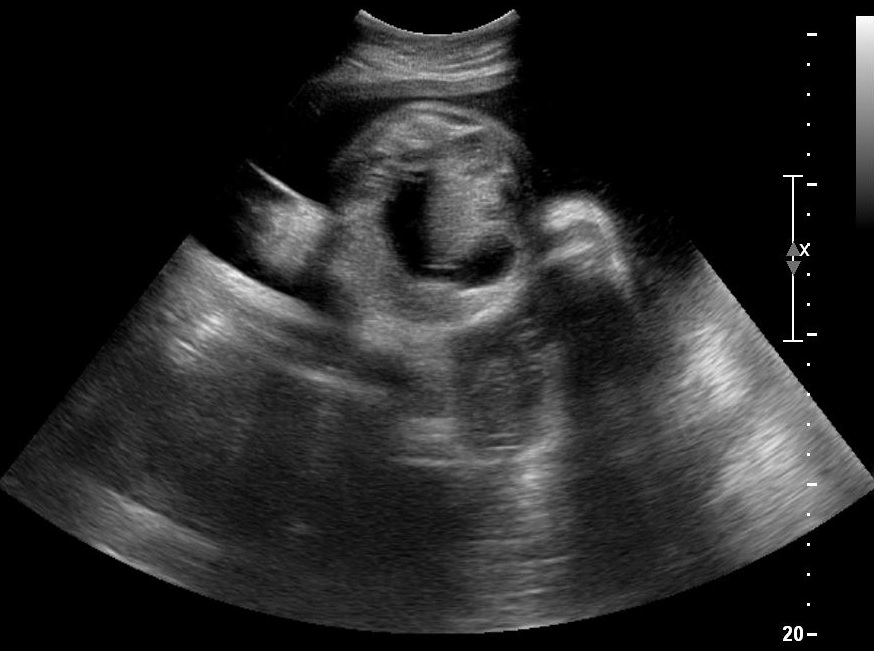

HomeGynecology Gynecology Vaginal Inclusion Cyst Laparotomy for Giant Ovarian Tumor Fallopian Tube Torsion Vesicovaginal fistula after hysterectomy Parasitic Myoma Smooth Muscle Tumor of Uncertain Malignant Potential (STUMP) Mucinous Cystadenoma Hysteroscopic Myomectomy Laparoscopic Excision of a Mesothelial Cyst of the Uterus Laparoscopic Treatment of A Chronic Ectopic Pregnancy Laparoscopic Removal of an intraabdominal IUD Paraovarian / Paratubal Cyst LAparoscopic Supracervical Hysterectomy (LASH) Laparoscopic Myomectomy Laparoscopic Management of Tubal Ectopic Pregnancy #2 Salpingectomy Laparoscopic Management of Tubal Ectopic Pregnancy #1 Salpingotomy Masterclass – Ultrasound Study of the Tubal Ectopic Pregnancy Total Laparoscopic Hysterectomy (TLH) Laparoscopic Management of an Immature Teratoma Ultrasound Study of Borderline Ovarian Tumors Laparoscopic Bilateral Salpingectomy: Tips & Tricks Transcervical Resection of the Endometrium Ultrasound Study of Cervical Cancer Pelvic Lymphoma Ureterovaginal fistula after hysterectomy Adenomyosis How to optimize your ultrasound image Hematometra after conization Endometrial Cancer Hemoperitoneum Endometrioma Infectious non-puerperal mastitis Hydrosalpinx Adnexal torsion Deep infiltrating endometriosis Struma ovarii Caesarean scar pregnancy Interstitial pregnancy Cervical pregnancy Share this: Share on X (Opens in new window) X Share on Facebook (Opens in new window) Facebook Share on LinkedIn (Opens in new window) LinkedIn